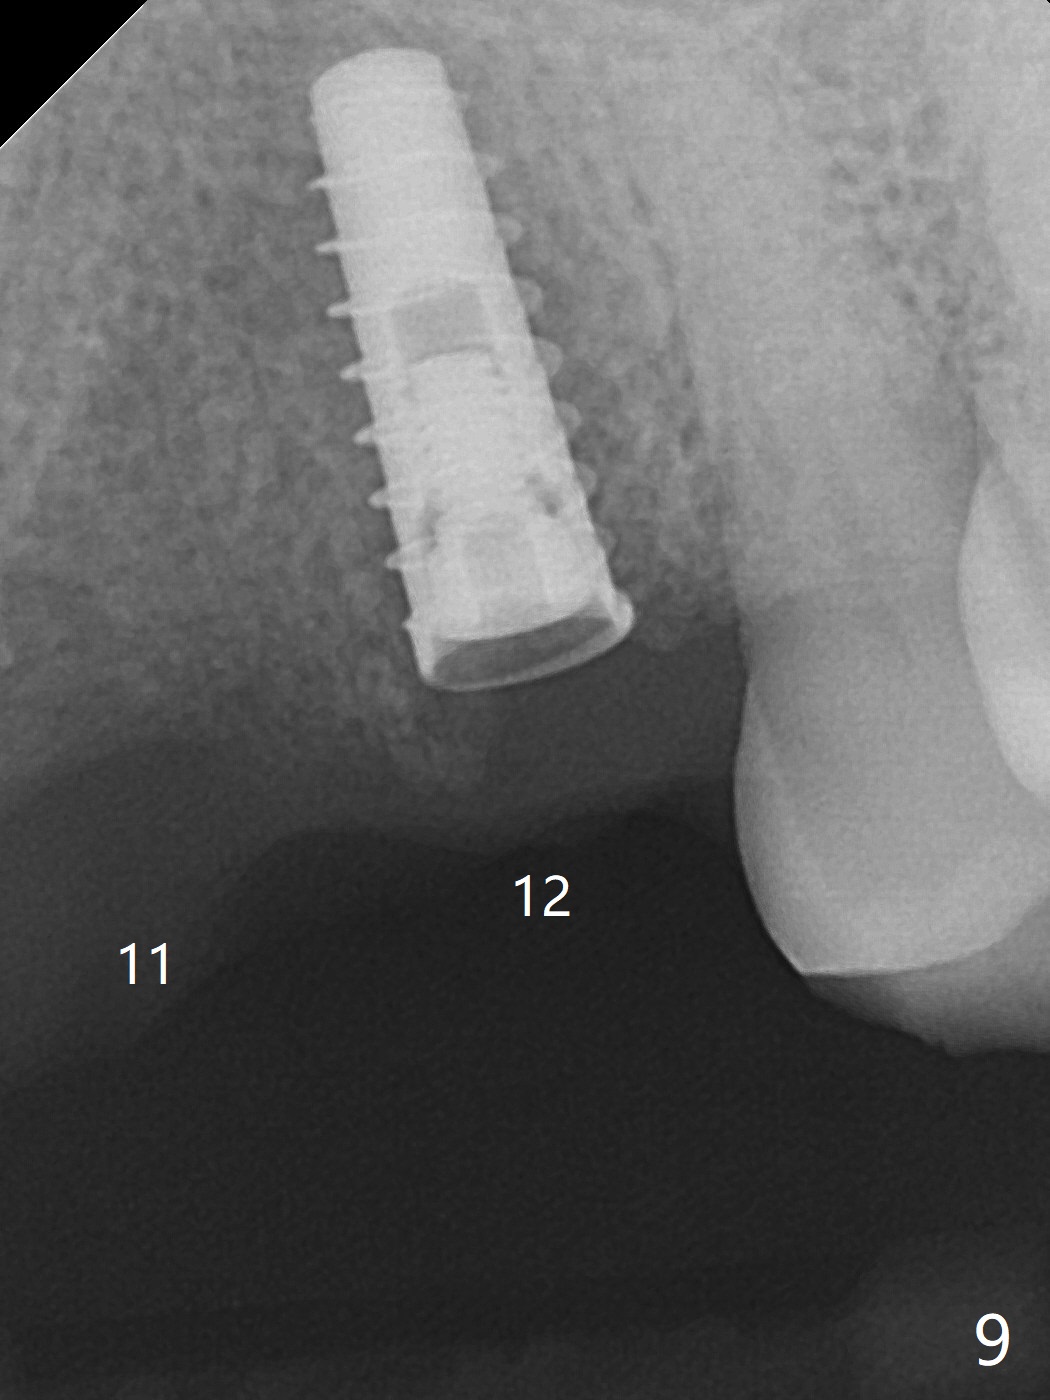

今天下午进入治疗室,粘性骨粉已制备:上清液来自红管(含促凝剂),离心3分钟(图一);再离心10分钟上清液就转变PRF,压制后,使用前剪成三块(图二:黑线),其中两块punch一个洞(图二:圆圈),插入7,9号牙基台固定;大块覆盖11/12号牙牙槽窝(图十四)。7,9,11,12号牙必须拔除(图三),然后在7,9,12种植。由于缺失左下磨牙,前牙垂直距离减少(图四)。完成9号牙位钻洞后,利用fixture mount(图五:M)植入植体,并留在原位固定导板(图六),然后7号牙种植,也留下fixture mount(图六:7,9),最后完成12号牙植入,但是后者扭力低,放置愈合螺帽(图九),而7,9号牙位放置修复基台(图七,八(使用5.5毫米profile drill后),好像基台没有完全就位。7号牙位更换基台似乎没帮助(图十),9号牙位再次放置同一个基台临床上仿佛有改变(比较图八与十二)。放置粘性骨粉后(图十一至十三),牙槽窝口覆盖PRF膜(图十四:P(A:基台)),最后使用树脂敷料固定骨粉和膜(图十五,六),基台帮助敷料固位,没有咬合干扰(图十七:*)。树脂敷料部分解决美观问题,一个月后撤除,如果植体仍有稳定性,可能制作7-10临时牙桥,可能部分维持或者恢复牙龈外形。术后一周病人主诉后面植牙和鼻底疼痛,11号牙根尖牙龈充血(图十八),轻度触痛,可能与术中尚未完全清创有关(图十九(术前CT 3D图像))。再服用Amoxicillin一周,症状好转,鼻底轻度触痛(图二十)。术后1.5月没有任何不适,撤除树脂敷料,7号牙基台(袖)显得太长,换一个短的(4.5x4(5)(图十,十一)->4x4(3)毫米)毫米),植骨好像愈合正常(图二十一:*)。7号牙换了短的基台,9号牙基台高度调整后,与对合牙有足够空间做临时牙桥,最好8,10号牙位牙龈应该凹陷(图二十二:*),有pontic外形。另外9号牙基台颊侧牙龈边缘有所修整,临时牙桥准备。先做7-10临时牙桥,理想临时牙桥pontic处树脂应该多些(图二十三:白线)压迫牙龈形成凹陷。11,12号牙牙槽窝在树脂(Bosworth)敷料下也正常愈合(图二十四)。